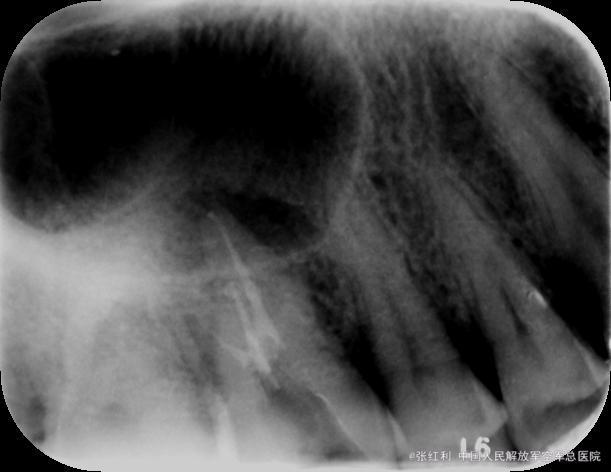

诊断:16牙周牙髓联合病变(逆行性牙髓炎) 治疗计划:16RCT+牙周基础治疗+改良翻瓣术 初诊:常规局麻下开髓揭顶,髓腔钙化,少量髓石,超声探查根管,拔髓,根管较细,疏通,封EDTA,一周后复诊。 复诊1:去暂封,继续探查根管,P、MB通畅,DB根尖区钙化,电测根长:P=MB=17.5mm,DB=15mm,EDTA下手扩+机扩+protaper根备至F2,生理盐水+双氧水反复交替冲洗,干燥,CP棉球+ZOE暂封,约日复诊。 复诊216消毒,局麻下洁治,刮治,小翻瓣术,搔刮出大量肉芽组织及少量牙石,根面平整,浓替硝唑冲洗,复位,OHI,约日复诊。 复诊3:腭侧窦道基本愈合,去暂封,超声荡洗,干燥,试尖可,糊剂+热牙胶根充,棉球+ZOE暂封,2周后复诊树脂充填。 复诊4:复诊常规树脂充填,腭侧窦道愈合(忘记拍片子,太遗憾,但是患者1个月后会过来复查)。

牙周牙髓联合病变的牙齿经常屋漏偏逢连夜雨,本身都已经很难治疗,还出现根管钙化不通,难以达到工作长度,但是遇到这种情况就放弃治疗了吗,当然不是,既然不通,可以不强行扩通,可以把目前能够做到的做到最好,看看预后,当然,这种情况得是病人理解并且配合,有的时候会有意想不到的收获,找个病例远中根尖没有到达工作长度,短期效果还是不错,期待长期效果,我还是抱了一定的希望的。